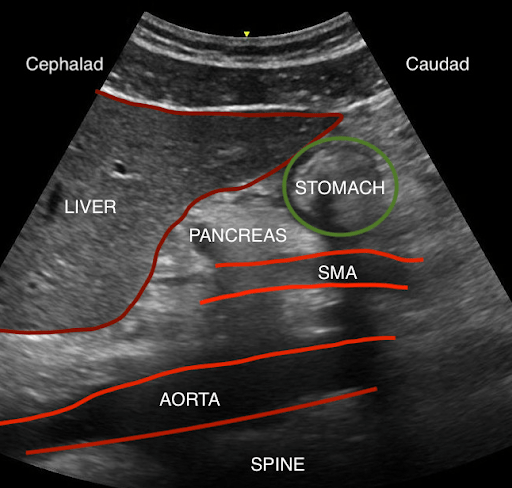

Often as we perform sonographic evaluation of the gallbladder and aorta, we pass over the pancreas and stomach, giving little consideration for the surrounding organs. In the world of anesthesiology, there has been a recent interest in using POCUS for assessing gastric contents in the perioperative period for patients taking a GLP-1 agonist for treatment of diabetes and obesity management to determine the incidence of retained gastric contents despite standard pre-operative fasting protocols.

Flynn et al. conducted a narrative review of the anatomy of the stomach and adjacent organs, exploring how ultrasound can be utilized to assess gastric content and predict the risk of pulmonary aspiration of gastric contents.